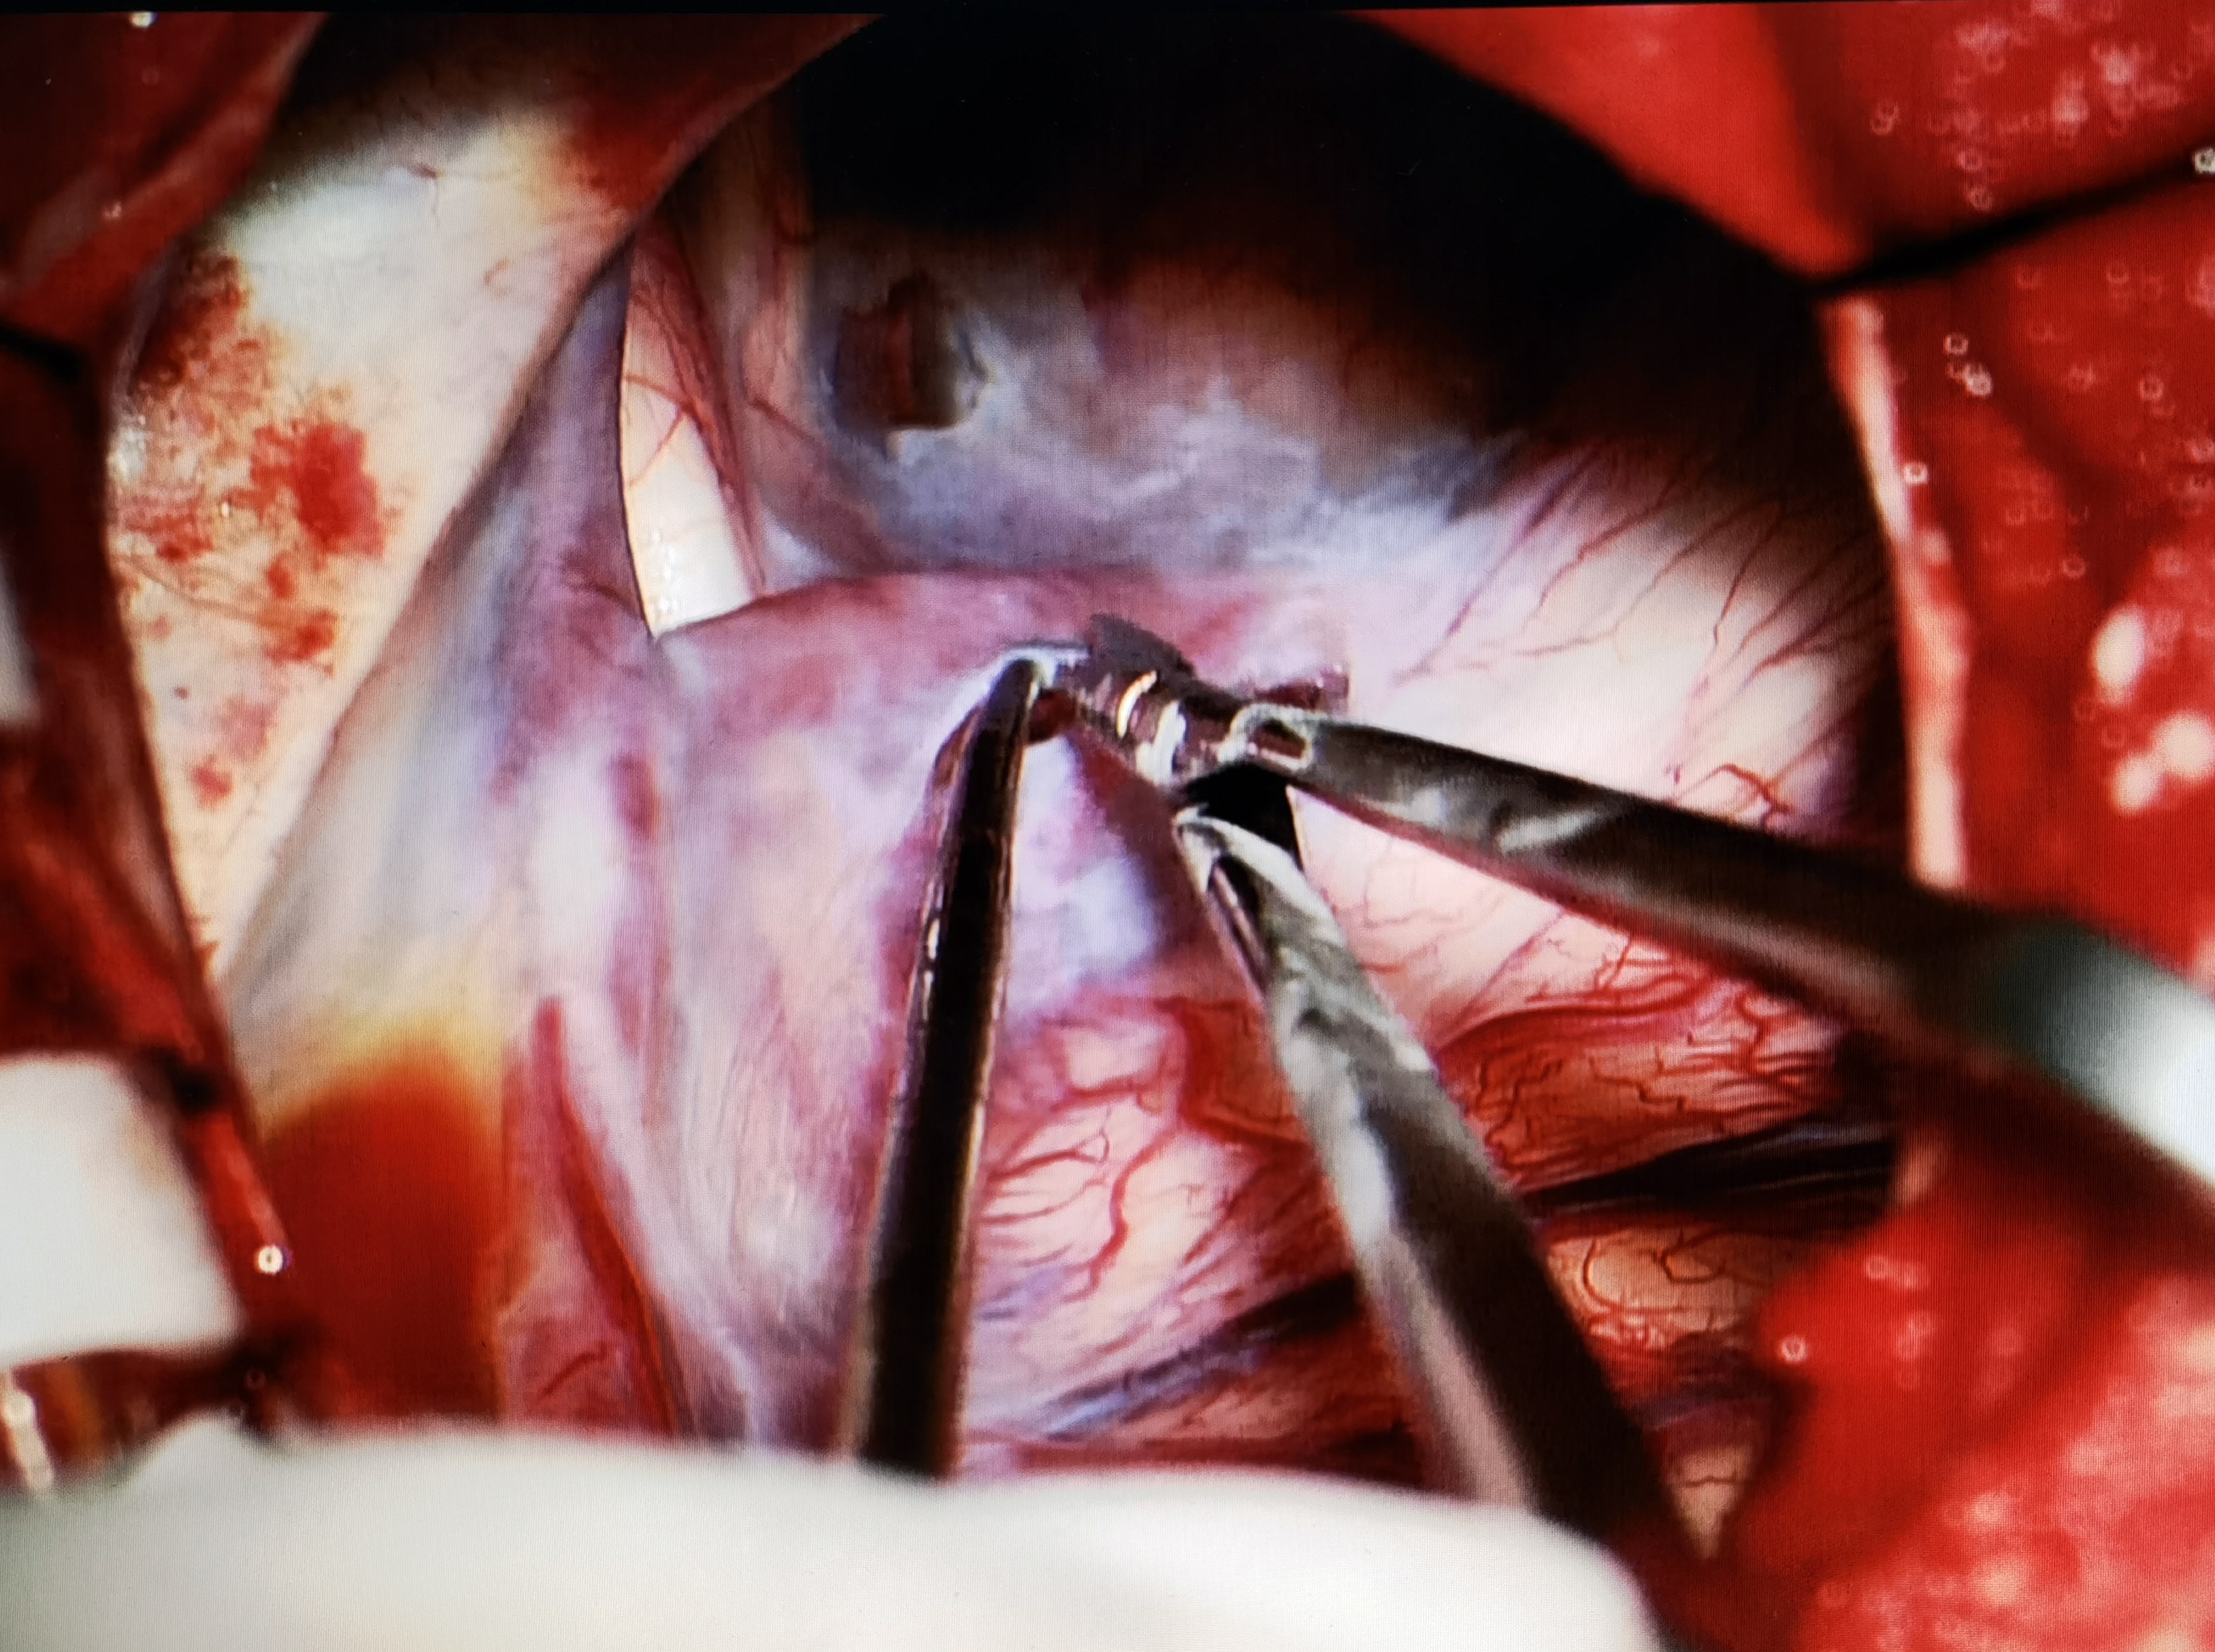

考虑到患儿囊肿体积巨大,占位效应明显,向患儿家属交代病情及手术风险后,行小骨窗开颅蛛网膜囊肿-脑池造瘘术,术中打通侧裂池、颈动脉池、基底池,多处造瘘,瘘口大小为1-1.5cm,并切除部分囊壁。术后患儿无新发症状,病情恢复良好,定期复查随访。

术中造瘘